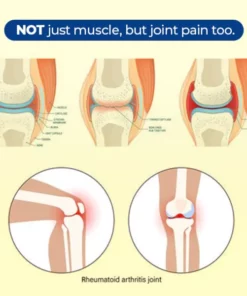

What causes cervical vertebra discomfort and Rheumatism joint pain?

On the other hand, rheumatism joint pain, which usually affects joints in the hands, wrists, and knees, occurs when autoimmune inflammation attacks the lining of the joint and causes swelling and damage to the joint tissue. This leads to chronic pain, unsteadiness, and in severe cases, deformity.

While the causes behind cervical vertebra issues and rheumatism are different, both can negatively impact a person’s quality of life and should require proper medical evaluation and treatment and pain management.